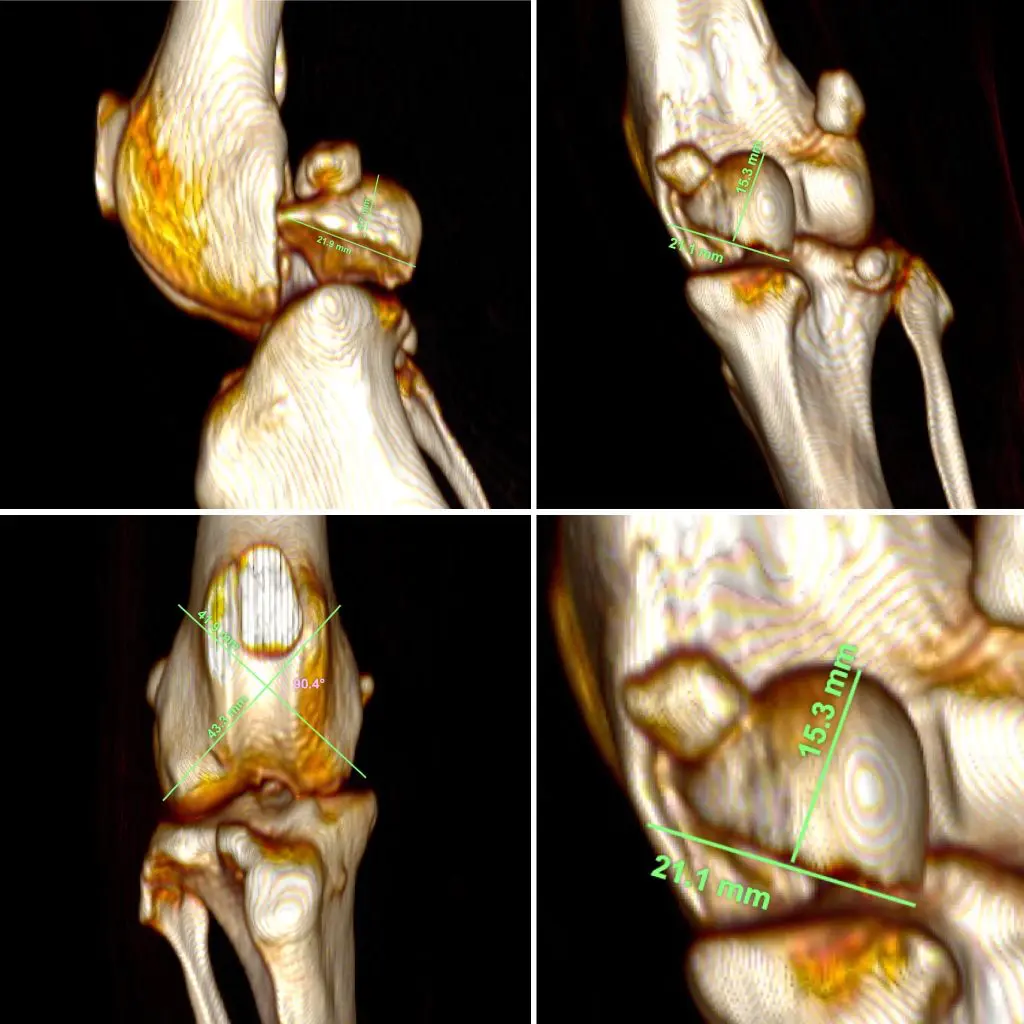

Como primer paso diagnóstico realizamos un estudio radiológico. En las radiografías se apreciaba una fractura femoral articular, aunque por su morfología es difícil de definir con precisión. Por este motivo, se decide completar el estudio con una tomografía computarizada (TC), herramienta fundamental en este tipo de lesiones complejas.

La TC confirma el diagnóstico: una fractura articular del cóndilo medial del fémur. Se trata de una fractura poco frecuente y especialmente compleja. La fractura compromete directamente estructuras articulares como el menisco medial y el ligamento cruzado anterior. Esto aumenta la dificultad quirúrgica y exige una correcta reconstrucción.